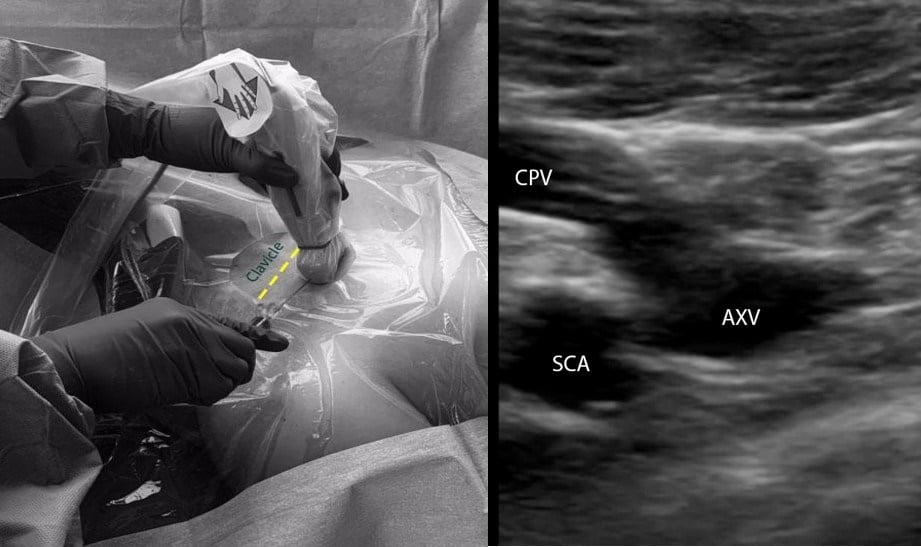

A. Infraclavicular in-plane approach (Figure 2):

- Position the patient in the supine or Trendelenburg position. The patient should be prepped and draped in the usual sterile fashion. The ipsilateral IJV and the contralateral SCV areas should also be prepped and draped.

- Place a linear transducer (6-13 MHz) in the infraclavicular fossa, approximately 2-3 cm distal to where the SCV courses below the clavicle.

- Obtain a long-axis view of the axillary vein and the distal SCV. Evaluate the depth, caliber, and patency of the axillary vein and the SCV.

- Use compressibility and/or pulse-wave Doppler to confirm that the structure visualized is indeed the vein, and not the artery.

- Insert the needle in the midpoint of the small footprint transducer using the in-plane approach. The needle should be advanced slowly, taking note of the lung pleura underneath the vessels.

- If needle visualization is lost, it is important to stop advancing the needle. Withdraw slightly and re-visualize the needle before proceeding.

- Once within the lumen of the vessel, insert the guidewire and monitor the guidewire placement in real time with ultrasound.

- Make a small incision on the skin, dilate the vessel, and insert the catheter over the guidewire.

Figure 2: Ultrasound-guided subclavian vein cannulation. AXV (axillary vein), SCA (subclavian artery), SCV (subclavian vein).